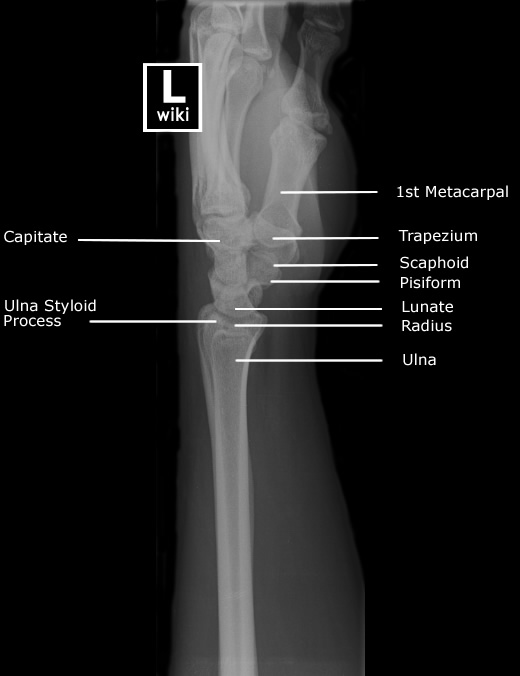

| Lateral View | Carpal tunnel View |

![]() |